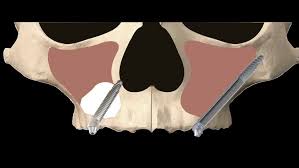

3. Zygomatic Implants

Zygomatic implants are a subtype of endosteal. They constitute another feasible alternative for patients lacking sufficient bone. This is because they are much longer than the standard endosteal and can be solidly implanted in the upper jaw bone (zygoma).